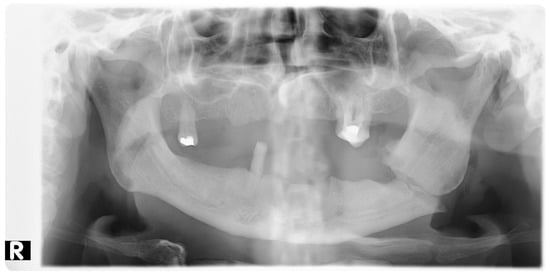

2. Materials and Methods